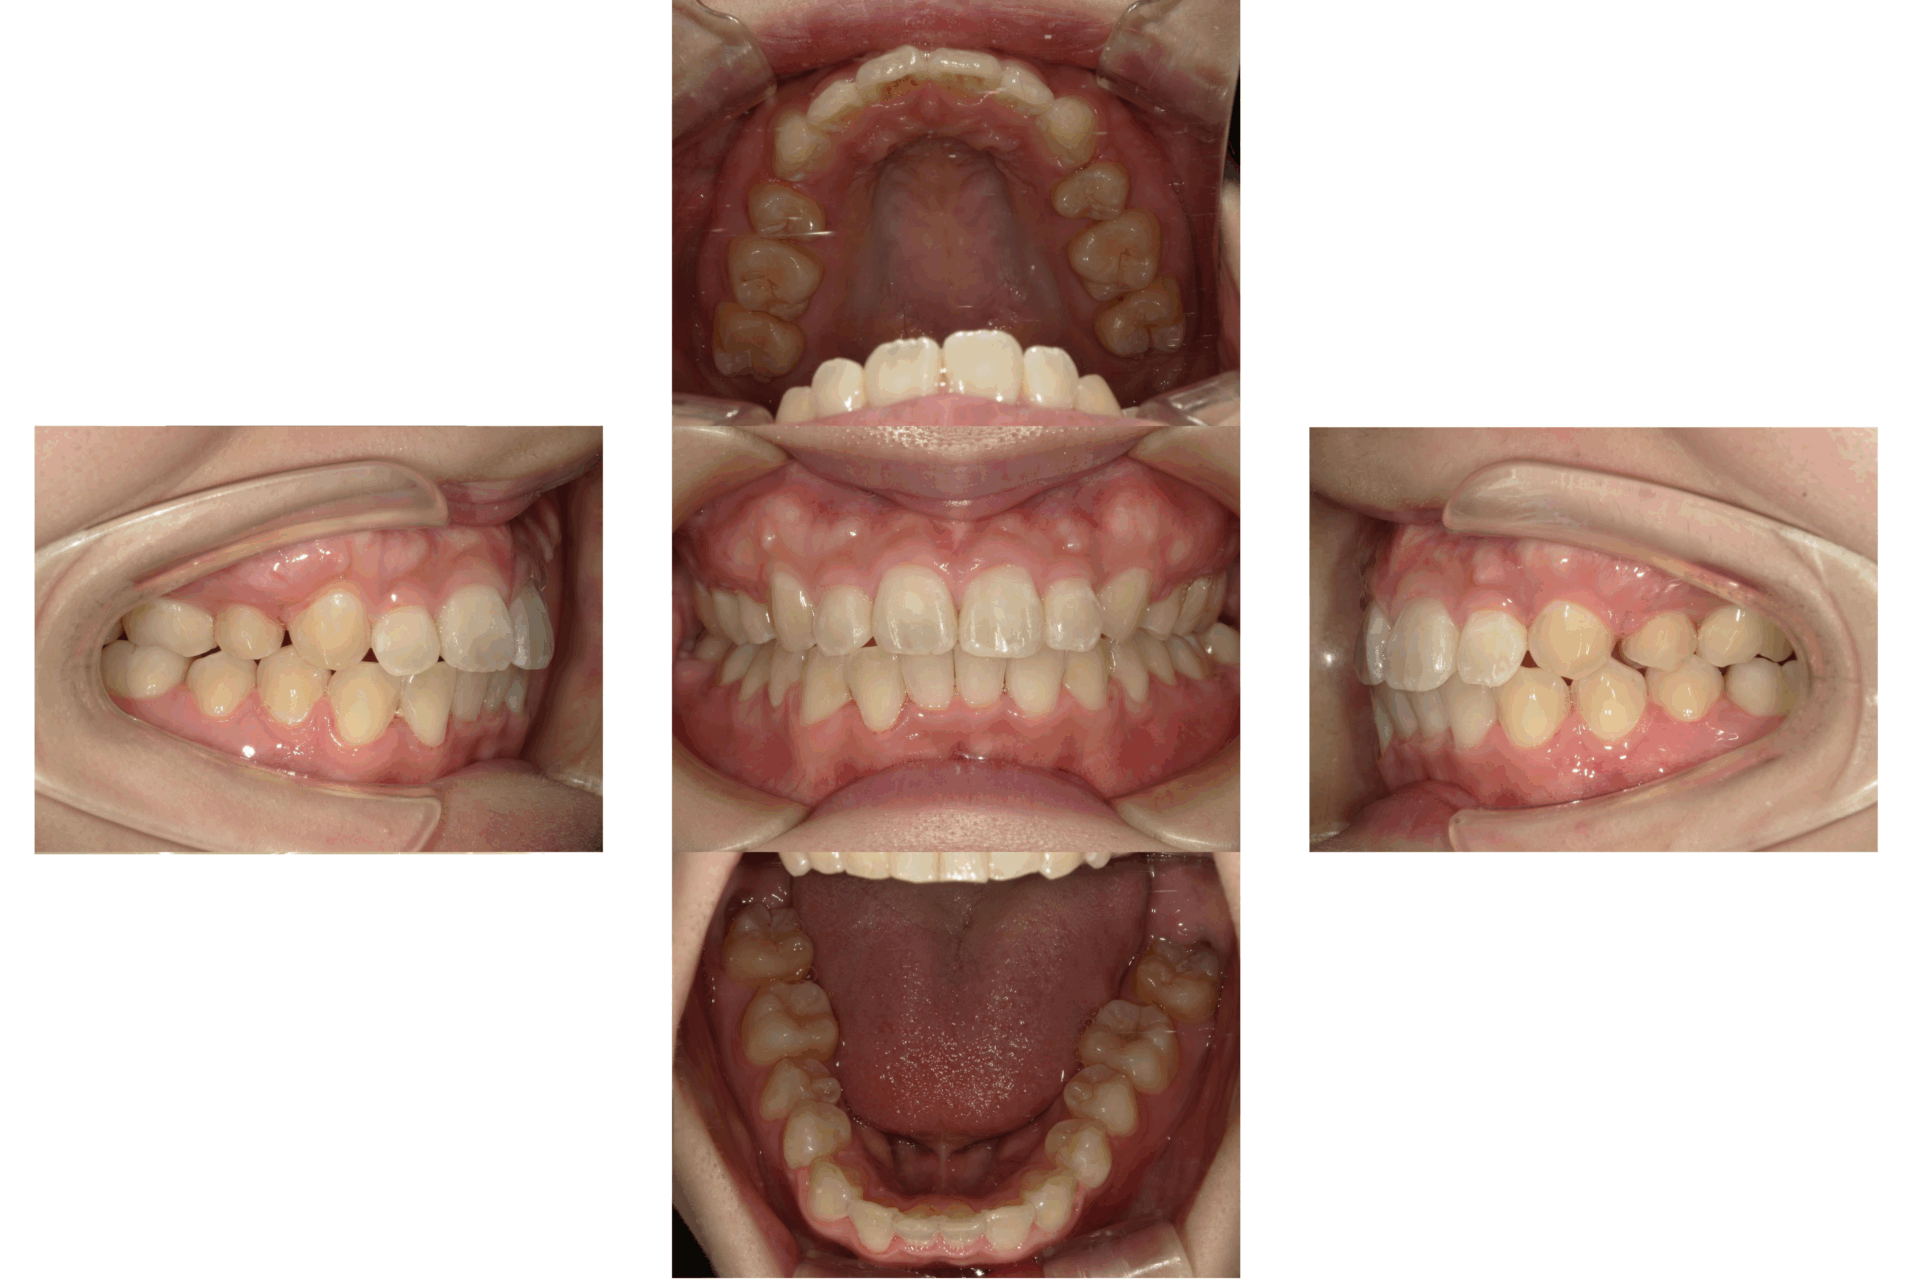

20代、男性、ワイヤー

| 施術内容 | 主訴:でこぼこで食べ物がよく挟まる。虫歯や歯肉炎に悩まされてきた。 詳細:ワイヤー矯正での歯並び改善 とても磨きやすくなったと満足されてます。 |

| 治療期間 | 16ヶ月(2/3現在 治療終了) |

| リスク・副作用 | ■リスク・副作用 ・治療の初期段階では、痛みや不快感が生じやすくなりますが、一週間前後で慣れます。 ・歯の動き方には個人差があるため、予想された治療期間より延長する場合があります。 |

| 費用 | ワイヤー矯正 60万円(税込660,000円) |